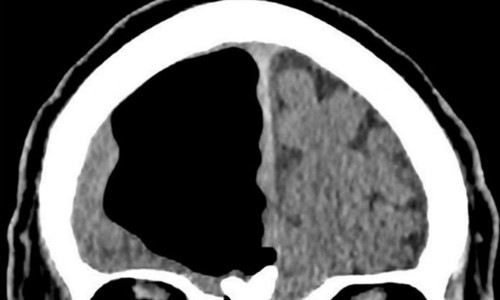

Hình ảnh chụp CT não của cụ ông cho thấy có lỗ hổng trống không. Ảnh: BMJ.

Kết quả chụp chiếu cho thấy thùy não trái của một cụ ông 84 tuổi (Bắc Ireland) bỗng nhiên biến mất, gây bàng hoàng cho các bác sĩ.

Nói cách khác, các bác sĩ cho rằng không có lý do nào dẫn đến tình trạng khác lạ của ông cụ, hoặc là họ đã thiếu sót ở khâu nào đó. Cuối cùng, họ cho ông chụp CT và MRI não. Kết quả khiến các bác sĩ sững sờ: Thùy não trái của ông cụ hoàn toàn trống không.

Các bác sĩ chẩn đoán cụ ông có thể đã bị pneumocephalus - một tình trạng có khí trong sọ. Hiện tượng tụ khí này thường xảy ra đối với những bệnh nhân phẫu thuật não. Nó cũng có thể xảy ra sau khi bị nhiễm trùng xoang, chấn thương đầu hoặc mặt, nhưng thường những túi khí nhỏ chứ không to như vậy. Trong trường hợp này, lỗ hỗng trong não bệnh nhân đo được khoảng 8,9 cm, chiếm gần trọn thùy não trái.